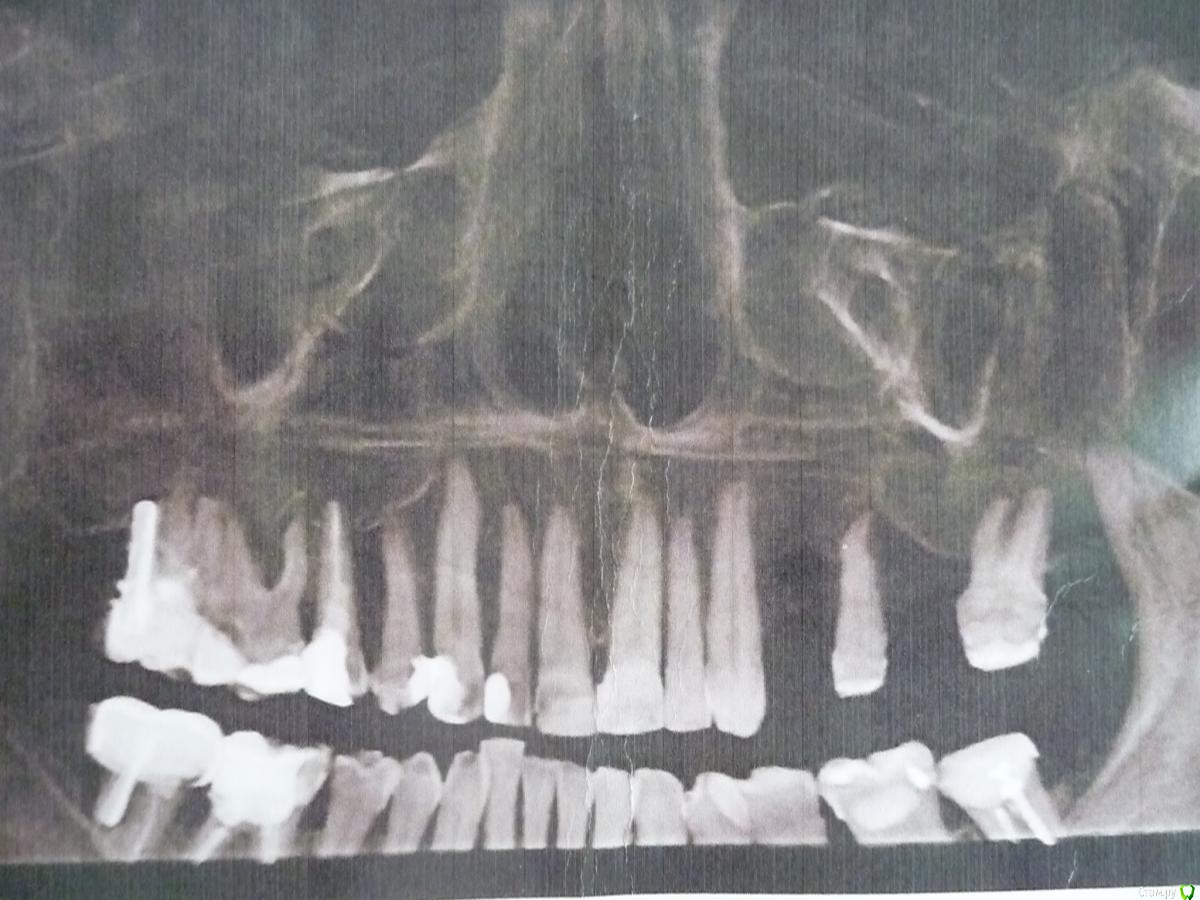

Уважаемые стоматологи! Помогите пожалуйста принять правильное решение НАДО ЛИ УДАЛЯТЬ КРАЙНИЙ ВЕРХНИЙ ЗУБ с ПРАВОЙ СТОРОНЫ.

1)    только удаление т.к. анкер стоит «снаружи» и  "ушла" кость.

2)     «сто лет» так было и еще столько же простоит, а если будет беспокоить, то удалить, что не критично т.к. стоящий перед ним зуб еще «живой», есть шанс его сохранить и тем самым сохранить справа свои жевательные зубы.

Зуб не беспокоит, но тревожит, что при удалении может быть нарушен, стоящий перед ним зуб.

И еще вопрос -  если этот крайний зуб сейчас не удалять, то какие НЕГАТИВНЫЕ ПОСЛЕДСТВИЯ могут быть.